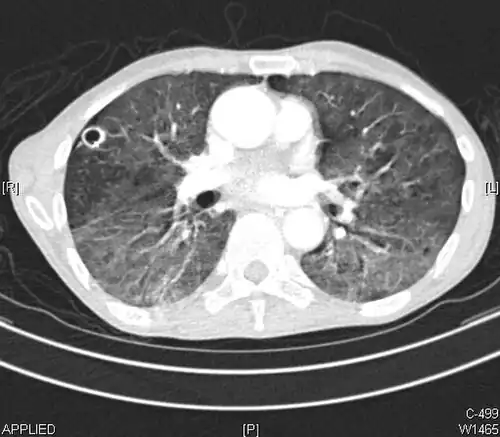

The crazy paving pattern may occur when there is both interlobular and intralobular widening. This sometimes resembles a road paved with irregular bricks or tiles. It is typically diffuse, involving larger areas of one or multiple lobes. There are a variety of potential causes, including Pneumocystis pneumonia, late-stage adenocarcinoma, pulmonary edema, some types of idiopathic interstitial pneumonias, diffuse alveolar hemorrhage, sarcoidosis, and pulmonary alveolar proteinosis.[6] COVID-19 has also been shown to occasionally cause GGOs with a crazy paving pattern.[11]

CT image showing crazy paving pattern of ground-glass opacities in both lungs.

Several studies have described a pattern among initial, intermediate, and hospital discharge imaging findings in the disease course of COVID-19. Most commonly, initial CT imaging reveals bilateral GGOs at the periphery of the lungs. During initial stages, this is most often found in the lower lobes, although involvement of the upper lobes and right middle lobe has also been reported early in the disease course.[16][18] This is in contrast to the two similar coronaviruses, SARS and MERS, which more commonly involve only one lung on initial imaging.[19][20] As the COVID-19 infection progresses, GGOs typically become more diffuse and often progress to consolidation.[11][18] This is sometimes accompanied by the development of a crazy paving pattern and interlobular septal thickening.[18] In many cases the most severe pulmonary CT abnormalities occurred within 2 weeks after symptoms began.[17] At this point, many individuals begin showing resolution of consolidation and GGOs as symptoms improve. However, some patients have worsening symptoms and imaging findings, with further increase in septal thickening, GGOs, and consolidation. These patients may develop lung "white-out" with progression to acute respiratory distress syndrome (ARDS) requiring treatment escalation.[17][21]